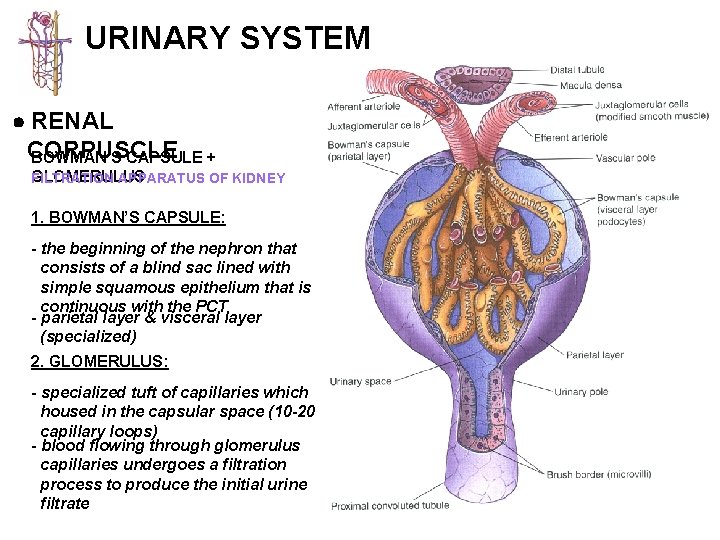

URINARY SYSTEM RENAL CORPUSCLE BOWMAN’S CAPSULE + GLOMERULUS FILTRATION APPARATUS OF KIDNEY 1. BOWMAN’S CAPSULE: - the beginning of the nephron that consists of a blind sac lined with simple squamous epithelium that is continuous with the PCT - parietal layer & visceral layer (specialized) 2. GLOMERULUS: - specialized tuft of capillaries which housed in the capsular space (10 -20 capillary loops) - blood flowing through glomerulus capillaries undergoes a filtration process to produce the initial urine filtrate

URINARY SYSTEM RENAL BOWMAN’S CAPSULE + CORPUSCLE GLOMERULUS FILTRATION APPARATUS OF KIDNEY VASCULAR POLE URINARY POLE GLOMERULUS (FILTRATION MEMBRANE): 1 - fenestrated capillaries; discontinuous endothelium; fenestrae have a diameter of 500 -1000Å and lack a diaphragm 2 - continuous basal lamina 3 - podocytes of visceral layer; processes contact basal lamina and are separated by slits measuring approximately 250Å